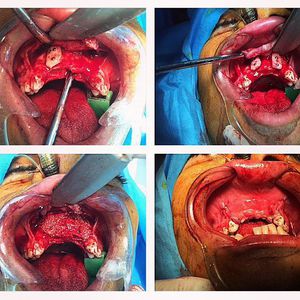

General knowledge: Maxillary augmentation denotes the genre of reconstructive surgeries that aims the correction of maxillary hypoplasia. Maxillary hypoplasia results from the underdevelopment of the maxillary bones and produces midfacial retrusion, creating the illusion of protuberance of the lower jaw. As a result the profile appears prognathic.Maxillary hypoplasia can affect different subunits of the maxillary bone. If the entire maxilla is hypoplastic, it is termed maxillary micrognathia, while premaxillary hypoplasia refers to the part of the maxillary bone between the lateral maxillary incisor fissures.Craniofacial anomalies, Apert syndrome, and Crouzon syndrome include maxillary and cranial hypoplasia.Sent by maxillofacial surgeon @nima__sadeghi ,with permission of the patient.